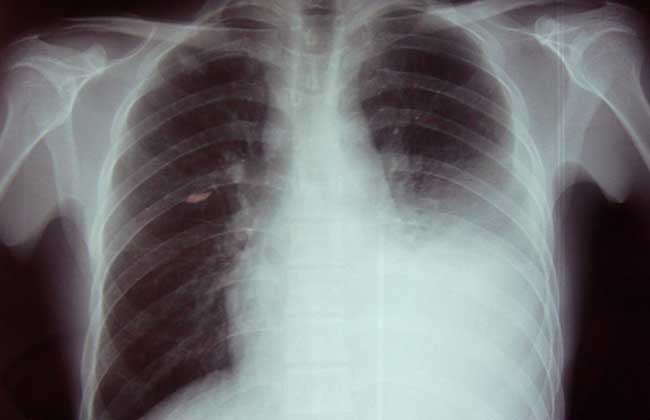

1、抗生素:抗结核药物治疗适用于结核性(干性或渗出性)胸膜炎的治疗,异烟肼、利福平、乙胺丁醇、链霉素交替使用,总计疗程6~9月。非结核性胸膜炎应针对原发病(如感染、肿瘤等)选择相应的药物治疗。化脓性胸膜炎或结核性脓胸伴感染者用青霉素治疗。

2、缓解疼痛:口服阿司匹林、消炎痛或可待因。

3、胸腔穿刺抽液:适用于渗出性胸膜炎胸腔大量积液、有明显呼吸困难或积液久治不吸收者。每次抽液量不宜超过1000毫升,每周2~3次。

4、激素治疗:激素治疗与抗结核药物联用,对消除全身毒性症状、促进积液吸收、防止胸膜增厚黏连有积极的治疗作用。可口服强的松,待全身症状改善,积液明显吸收时,逐渐减量,用药4~6周。